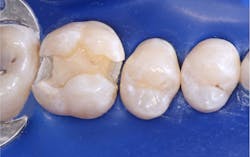

A direct pulp cap is performed when the pulp is exposed during caries excavation, and it’s bleeding. The various definitions of when and if to do a direct pulp cap are extremely variable. Based on hundreds of direct pulp caps with impressive success, these are my criteria for performing a direct pulp cap (figure 3):

- The exposure is small, 0.5 mm to 1.0 mm in diameter.

- The blood coming from the exposure is normal-looking red blood—not magenta, which might indicate a hyperemic pulp.

- The blood is coming slowly from the exposure, not gushing out.

- You can stop the bleeding by gently placing a cotton pellet on it for a few seconds.